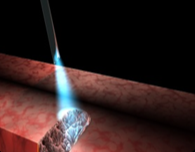

The Hemera Thulium Laser offers high-speed performance regardless of the size of the gland, vasculature and morphology. the surgeon can, then, choose whether to use vaporization, vaporesection or technical enucleation

Hemera Thulium Laser remains effective even after many passages. Thulium laser is superior due to the possibility to emit both in continuous and pulsed mode. A continuous emission with the ability to vaporesect with lower costs due to the possibility of using multiple – time reusable fibers instead of disposable ones.

Hemera Thulium Laser emits energy more efficiently and more predictably on targeted tissue, independently from their blood percentage. The optical penetration depth is uniform. The technique of laser coagulation with Hemera Thulium Laser can be performed by directing the laser beam directly on the blood flow. The side effects of postoperative bleeding and dysuria are way inferior to those of each other laser method.